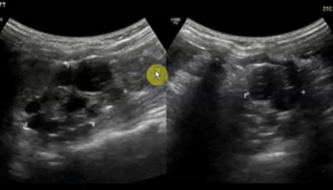

What grade of hydronephrosis is this?

Fluid extends into major and minor calyces. "Bear Claw" or

"Cauliflower" effect.

Grade 2